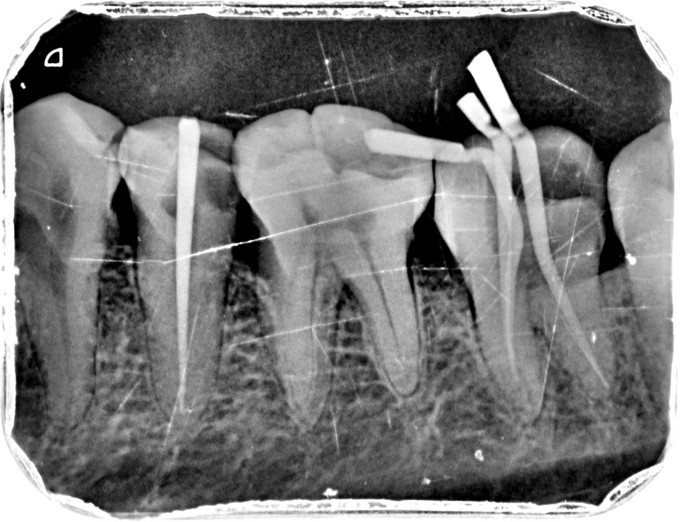

临床检查:35远中充填物部分脱落,探疼(+),冷(++),叩(-),松动度(-),牙石I度 37远中邻面龋坏至髓腔,探痛(+),可探及穿髓点,无窦道,叩(-),松动度(-),牙石I度 辅助检查:X线示35,37龋坏累积髓腔,牙槽骨部分吸收,根尖周组织无明显异常。

诊断:35,37牙髓炎 治疗:经患者知情同意后,35,37局麻去腐降牙合,开髓拔髓寻找根管口,建立直线通路,扩通根管,确定工作长度。S3/EDTA凝胶镍钛器械,低浓度次氯酸钠冲洗根管,预备至25/06,试主尖X线示恰充,试干根管,导AH-PLUS糊剂,VDW热压胶垂直加压根充,术后见根管恰充,暂封观察进行桩冠修复,对患者进行牙周治疗,口腔宣教。